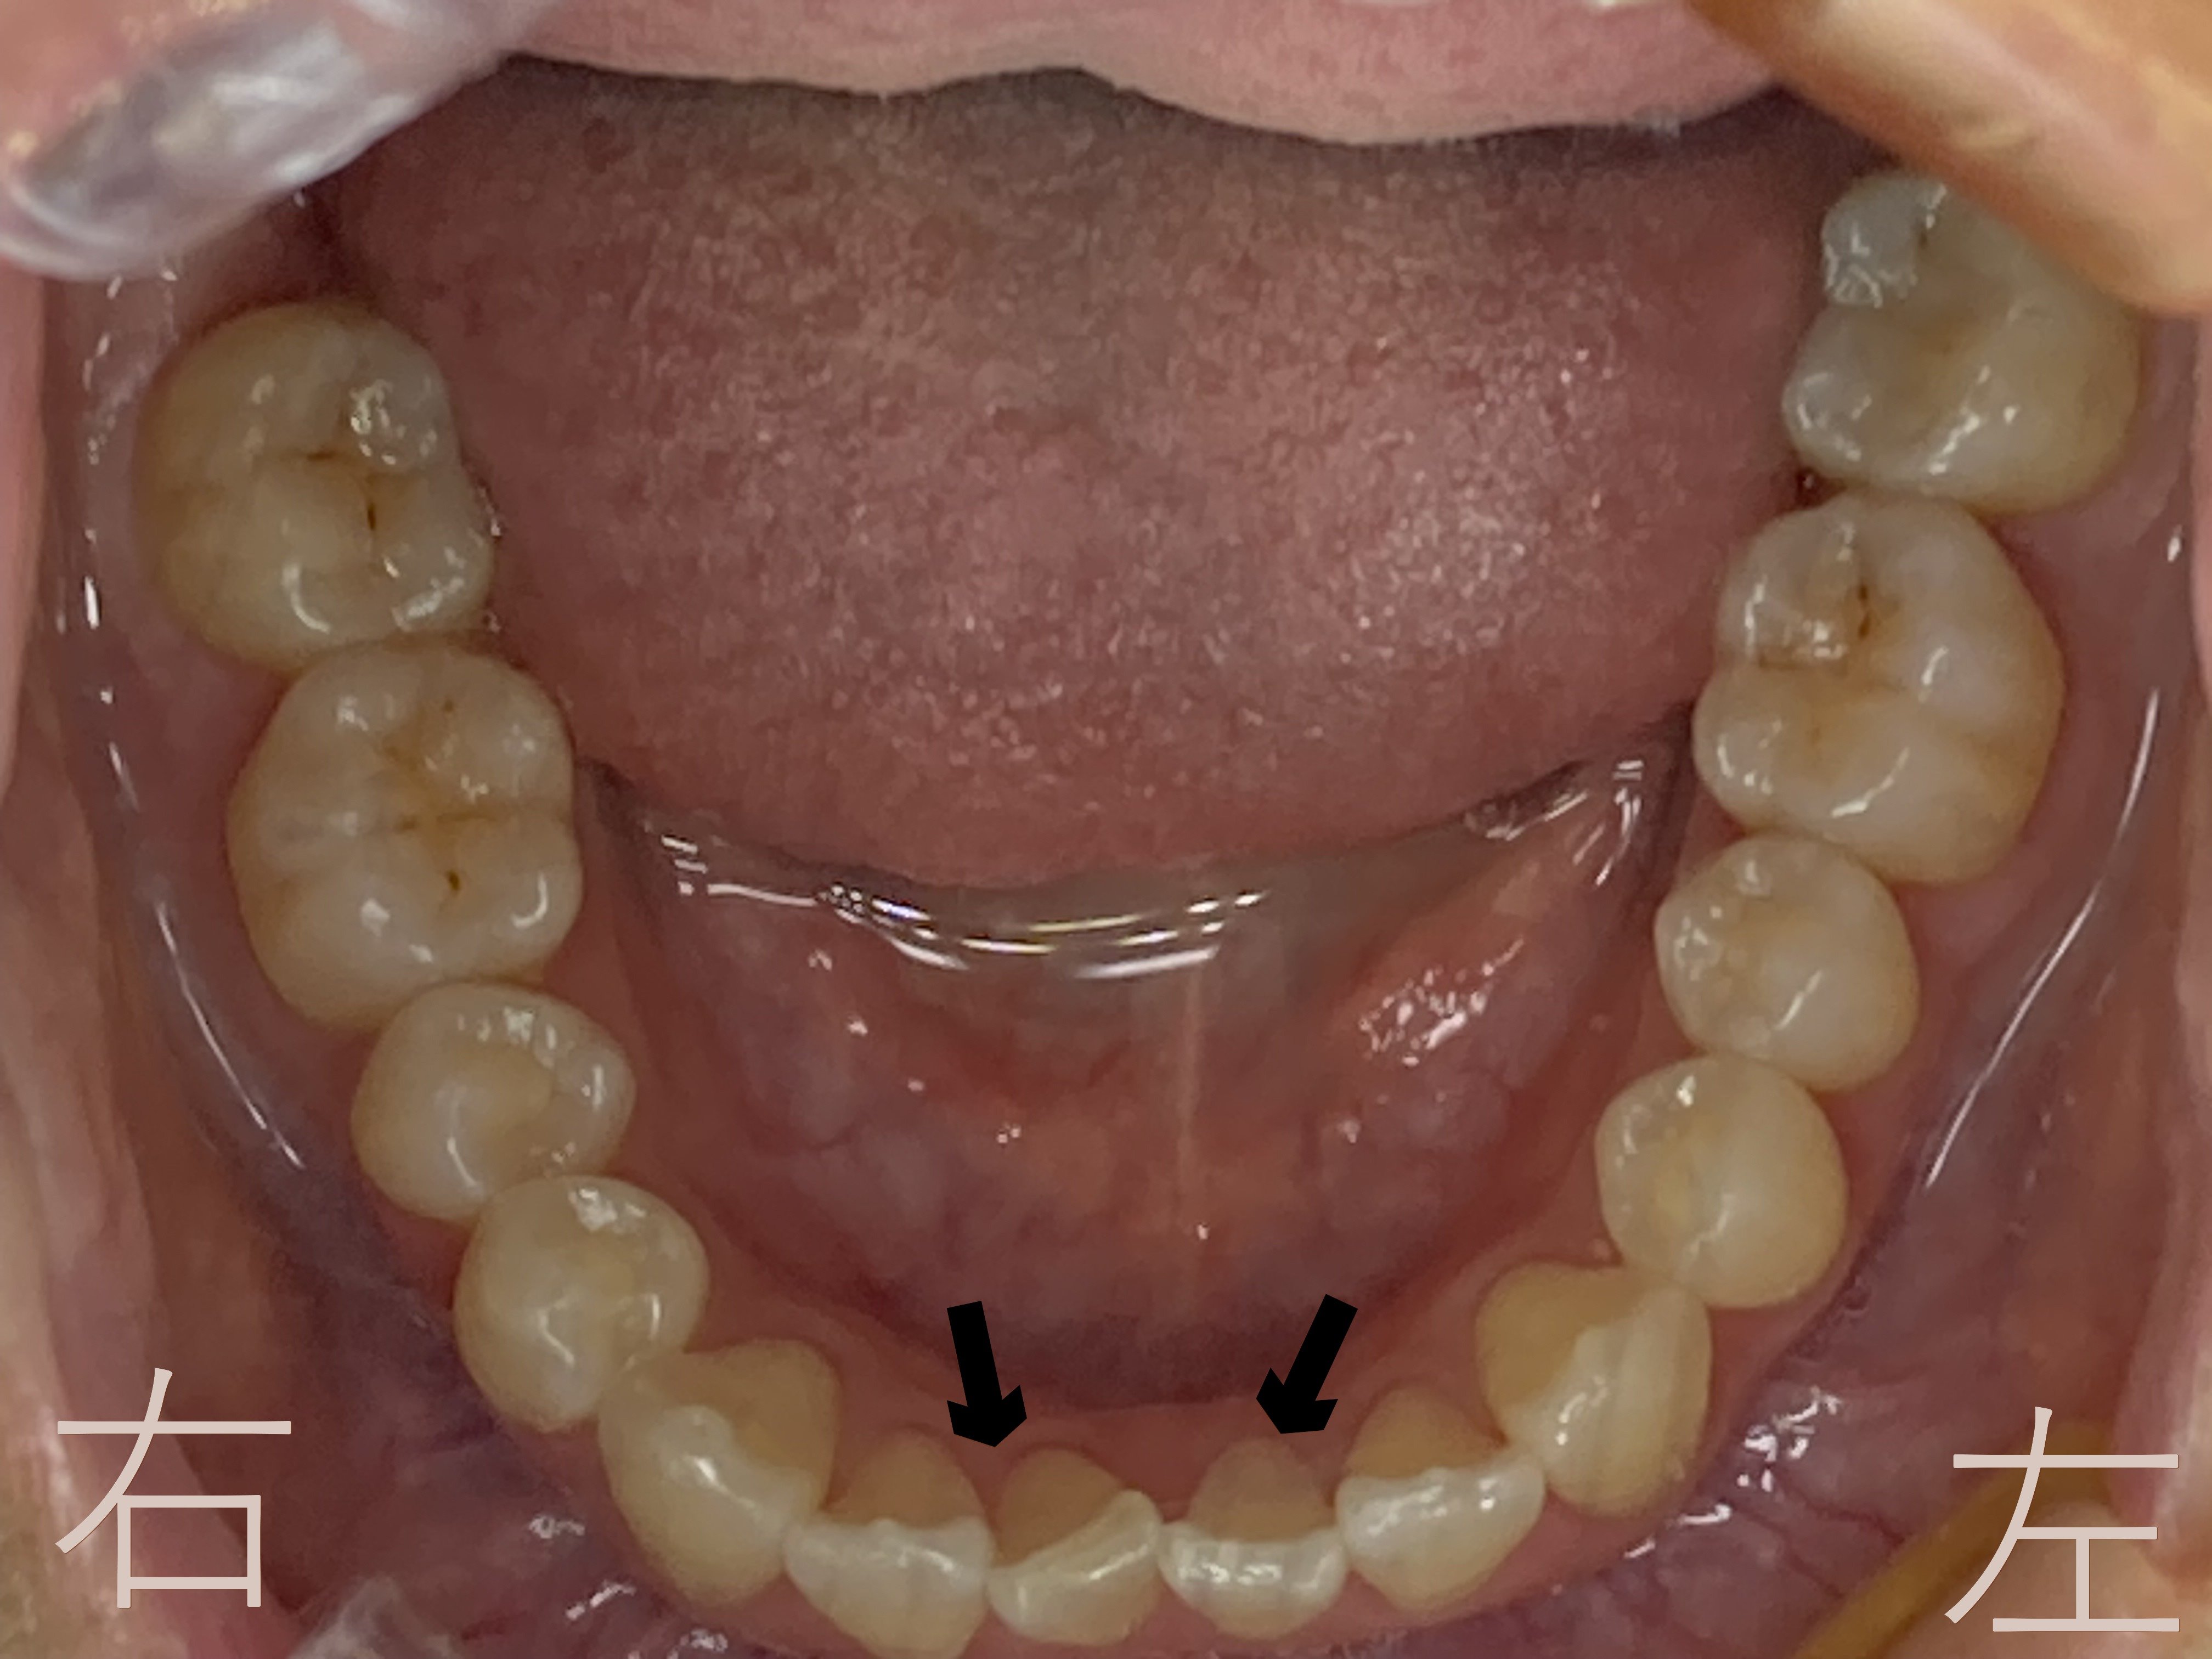

上記写真をご覧ください。下顎前歯部(黒色矢印)に歯のゆがみ【叢生】が認められます。

上記は8か月後の下顎の咬合面観です。黒色矢印の下顎前歯(黒色矢印の部分)のゆがみ【叢生】が解消されているのが確認できます。